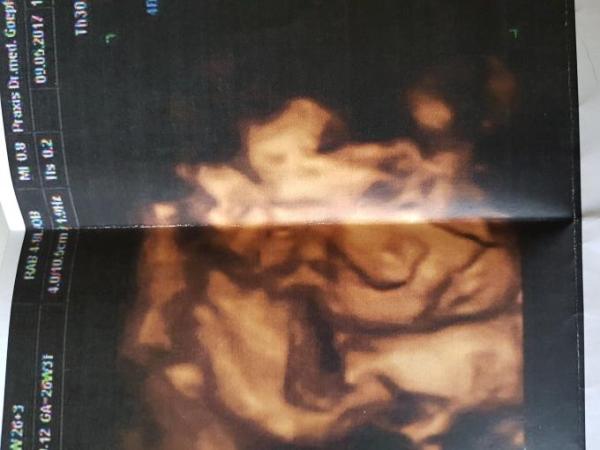

Die Maus ist bestens versorgt bisher. Bei 35 cm hat sie 930 g..... bin heute 26+3. Doppler ging wieder nur auf einer Seite, diesmal links, und der war auch okay. Und irgend so ein Quotient sagt aus, dass die nächsten 6 Wochen keine Gefahr einer Gestose besteht. Jaaaa..... und alle 2 Wochen wollen sie mich weiterhin sehen. Obwohl ich ja auch alle 2 Wochen zum KH soll..... mal sehen, was die morgen im KH dazu sagen...... Schönen Tag euch noch......

Bild zu Fa Termin heute...... - Forum für August - Mamis